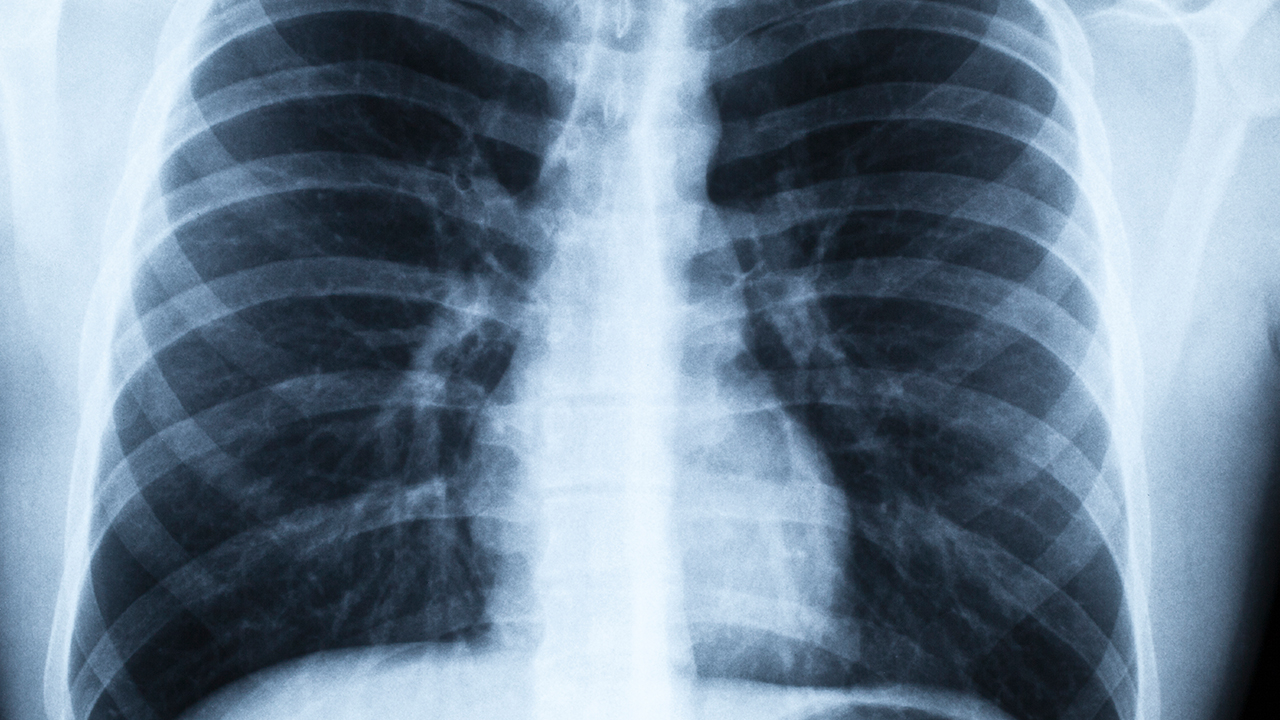

肺癌作为高发恶性肿瘤,其治疗需要多学科协作。济南作为山东省会,拥有多家具备肺癌综合诊疗能力的三甲医院,在手术、放疗、化疗及靶向治疗等方面各具特色。

肺癌预防需要重点关注高危人群的筛查。长期吸烟者、有肺癌家族史人群、接触石棉等职业暴露者应定期进行低剂量CT检查。戒烟是预防肺癌有效的措施,戒烟10年后肺癌风险可降低50%。保持健康饮食,多摄入新鲜蔬果,避免厨房油烟暴露也有助于降低肺癌发生风险。出现持续咳嗽、痰中带血、胸痛等症状时应及时就医检查。